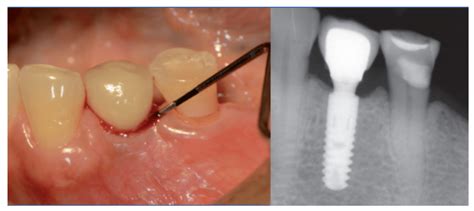

Si nota uno o varios de los síntomas anteriores, debe concertar una cita con su dentista y no intentar diagnosticarse usted mismo. Para el diagnóstico, el dentista necesita la llamada sonda periodontal. Tiene el aspecto de una fina punta metálica con la que el dentista puede medir la profundidad de la bolsa. La profundidad de la bolsa es el surco natural entre el diente y la encía, que tiene hasta 3,5 milímetros de profundidad en un estado sano. Esta suposición puede confirmarse con una radiografía.

La presencia de tejido blanco alrededor de la pieza es síntoma de rechazo del implante dental porque quiere decir que existe una infección. Las periimplantitis son infecciones que atacan a los tejidos blandos que sujetan el implante y que ocasionan su pérdida.